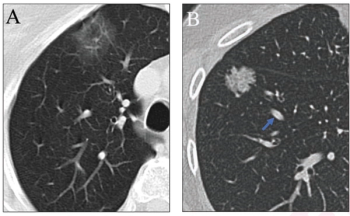

In comparison to standard-dose lung CT, the combination of deep learning image reconstruction with ultra-low-dose CT offered similar detection and characterization of pulmonary nodules at a nearly 93 percent reduction of radiation dosing, according to new research.